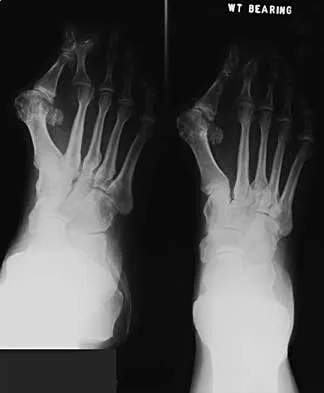

A 43-year-old man reports a 3-year history of progressively worsening pain in the first metatarsophalangeal joint that is aggravated by activity. Larger shoes, intra-articular corticosteroid injections, and a Morton's extension pedorthic have failed to provide relief. Motion is limited to 10 degrees of dorsiflexion, and the "grind test" is positive. An AP radiograph is shown in Figure 39. What is the most appropriate surgical treatment?

Explanation

A 50-year-old woman has a painful hallux valgus and a painful callus beneath the second metatarsal head. A radiograph is shown in Figure 46. To correct these problems, treatment of the great toe deformity should consist of